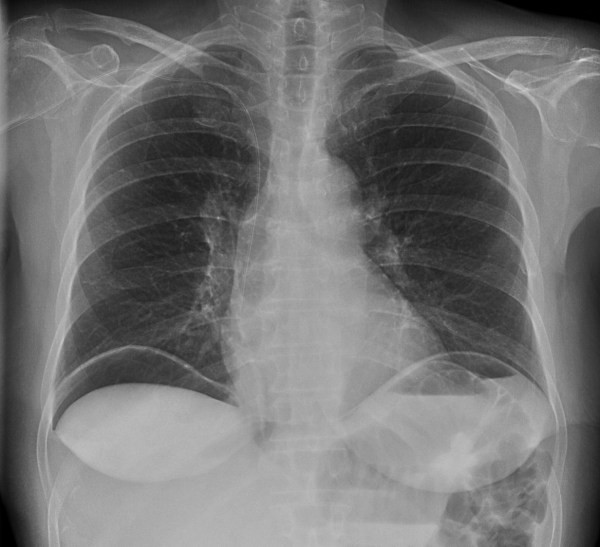

CASO: Febrícula y tos de 4 días de evolución.

Hallazgos:

- En la placa PA se observa una asimetría en los hilios pulmonares, el hilio izquierdo tiene una densidad aumentada.

- Tras examinar la placa lateral se observa un aumento de densidad en la columna que puede ser compatible con una condensación, es el signo de la desnificación vertebral.

SIGNO DE LA DENSIFICACIÓN VERTEBRAL: En la radiografía lateral normal, la densidad de la columna torácica tiende a disminuir desde la parte superior hasta el diafragma; la alteración de ese patrón por la presencia de una densidad superpuesta a la columna, indica la existencia de una consolidación pulmonar. Este signo adquiere especial valor cuando en la proyección posteroanterior la consolidación está oculta en el espacio retrocardíaco o en la base pulmonar.